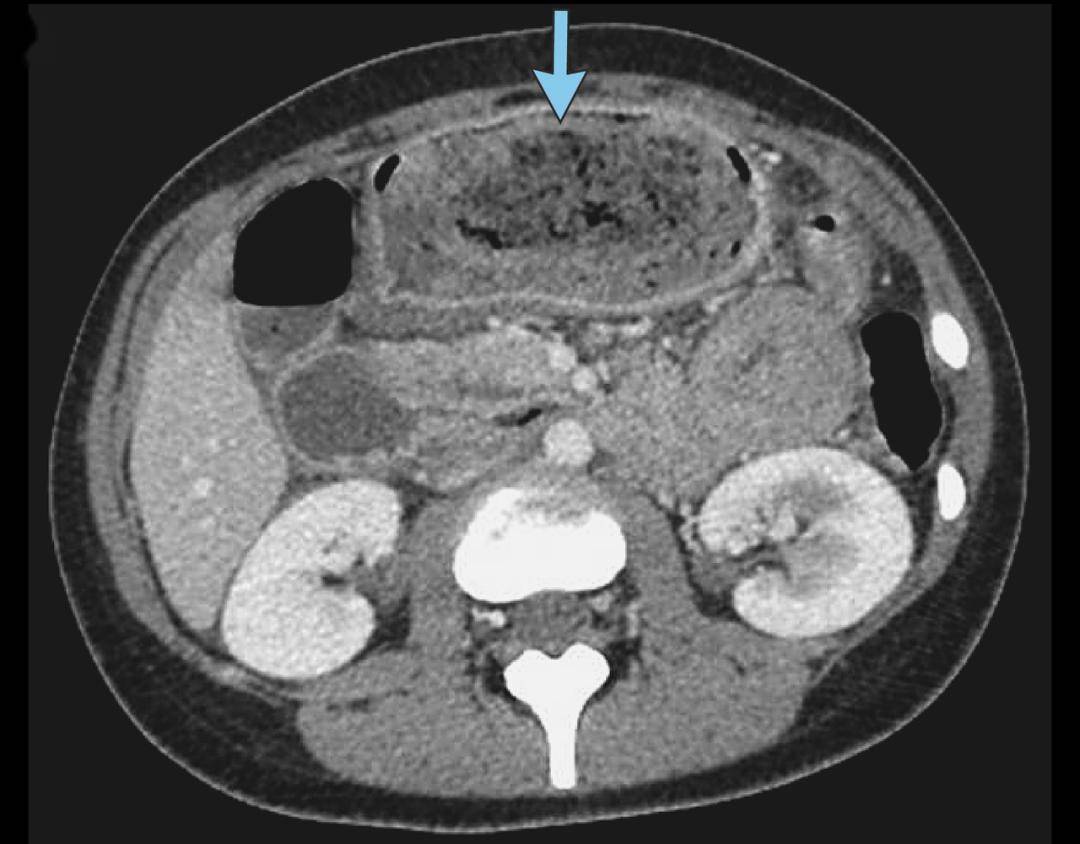

左滑查看更多图片:胃石示意图、手术中看到的毛发性胃石、CT检查中的胃石 | 参考文献[1]